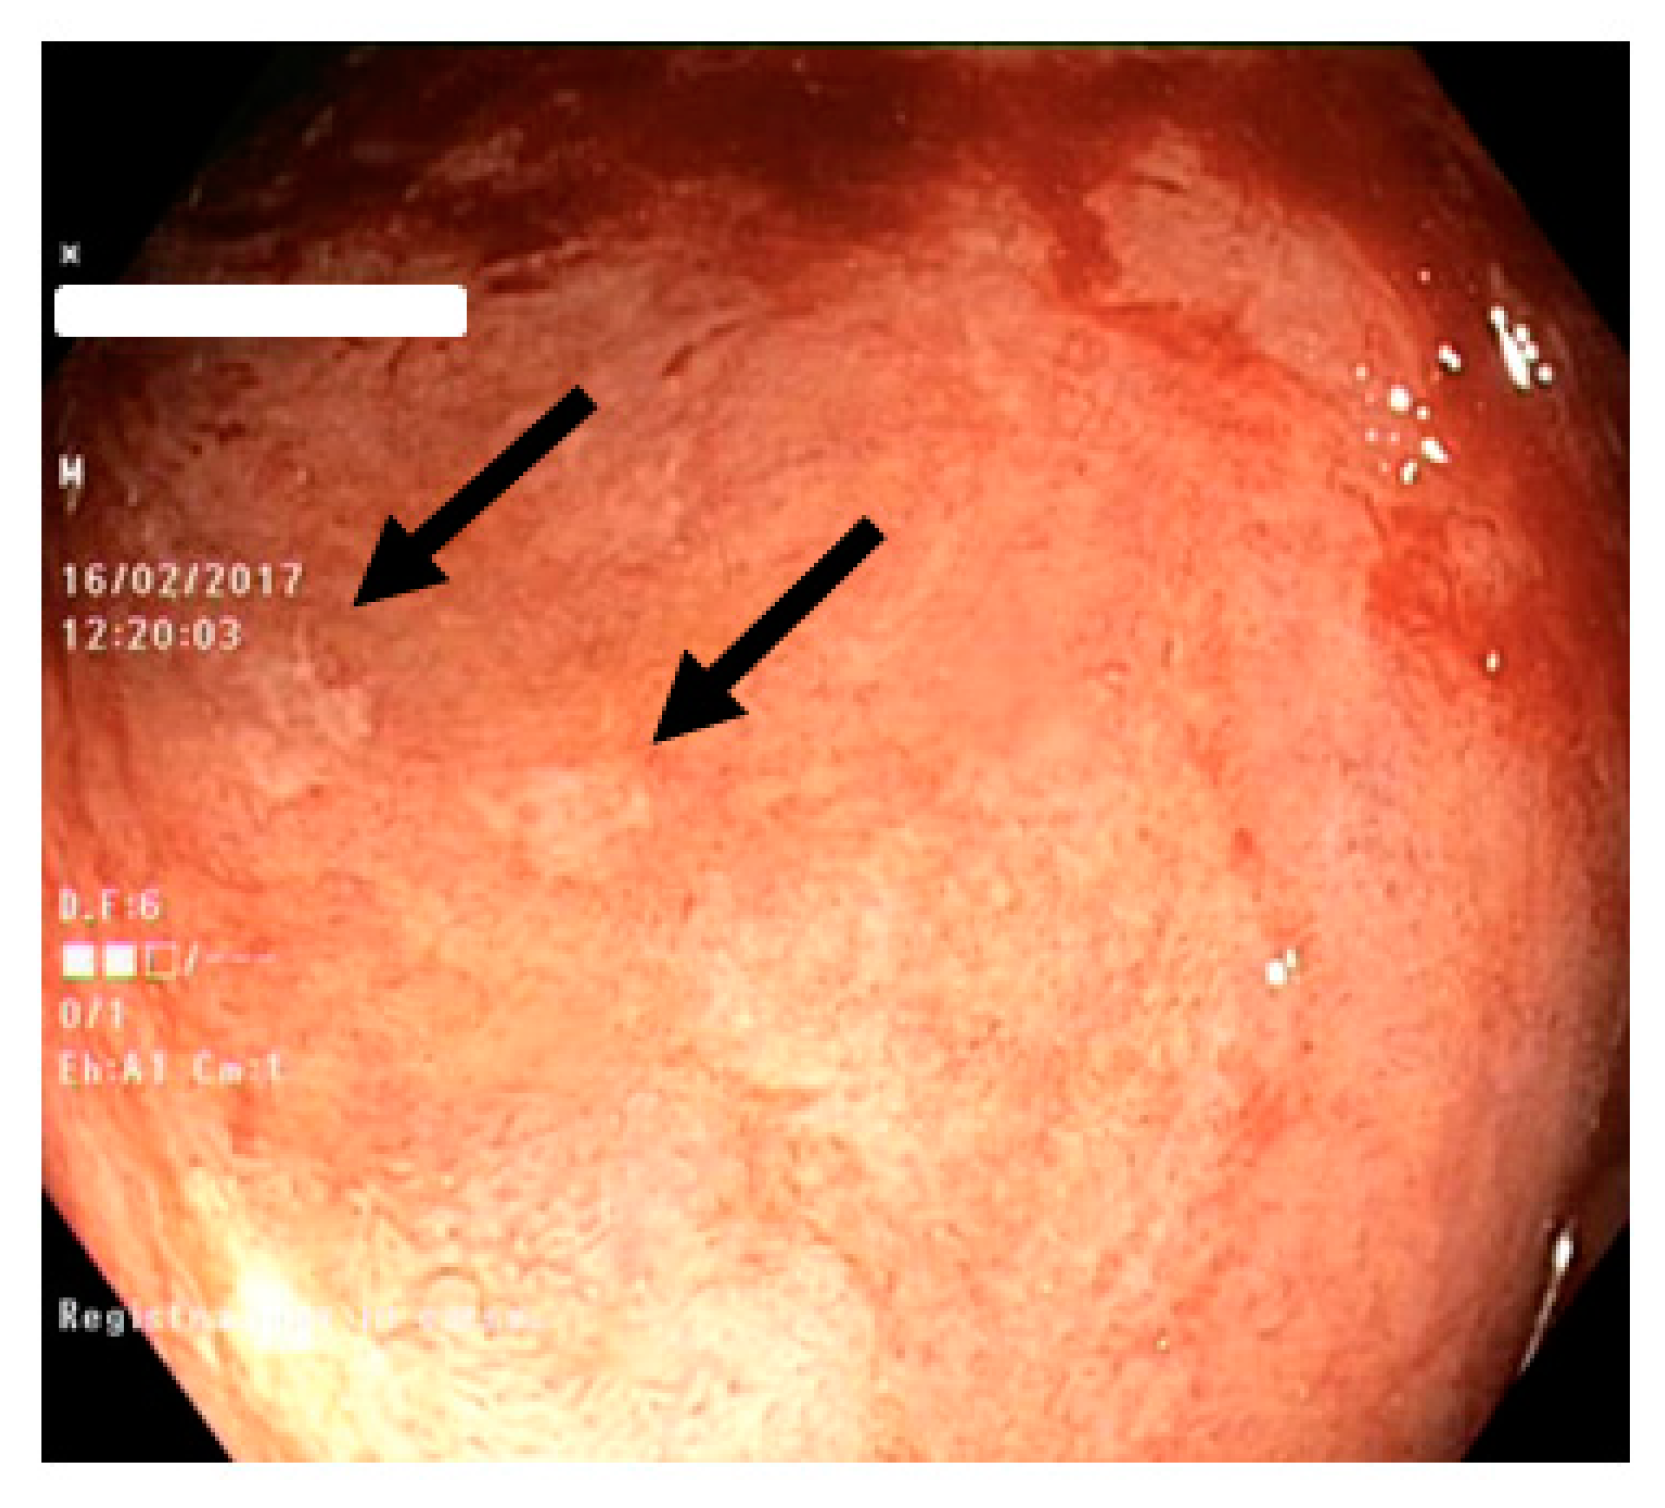

2.2. EMES

- erythema (0: absent, 1: mild, 2: moderate, 3: severe)

- submucosal vascular pattern (0: normal, 1: reduction, 2: disappearance)

- erosions (0: absent, 1: from 1 to 5 lesions, 2: from 6 to 10, 3: more than 10)

- ulcers (0: absent, 1: from 1 to 5 lesions, 2: from 6 to 10, 3: more than 10).